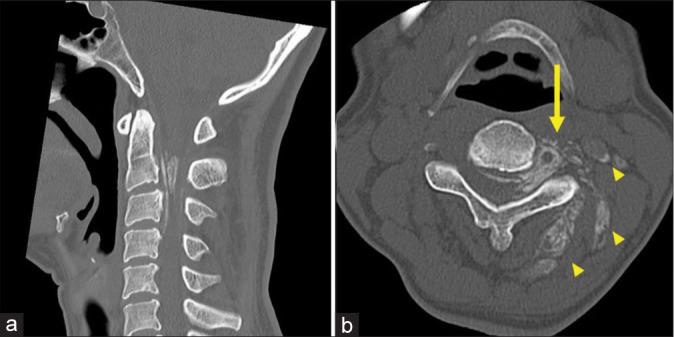

A 51-year-old woman presented with progressive paresis in both the upper and lower limbs. Magnetic resonance imaging revealed an extradural lesion at the C2-C4 level with homogeneous contrast enhancement. The lesion extended from the intervertebral foramen into the posterior cervical musculature. Computed tomography demonstrated diffuse calcification, spanning from the spinal canal to the posterior cervical musculature. The patient underwent tumor resection and decompression surgery, which led to an improvement in her neurological symptoms. Pathological examination confirmed the diagnosis of a psammomatous meningioma.

一名51岁女性出现双上肢和双下肢进行性无力。磁共振成像显示C2 - C4水平硬膜外病变,呈均匀强化。病变从椎间孔延伸至颈后肌肉组织。计算机断层扫描显示从椎管至颈后肌肉组织弥漫性钙化。患者接受了肿瘤切除减压手术,术后神经症状有所改善。病理检查确诊为砂粒体性脑膜瘤。